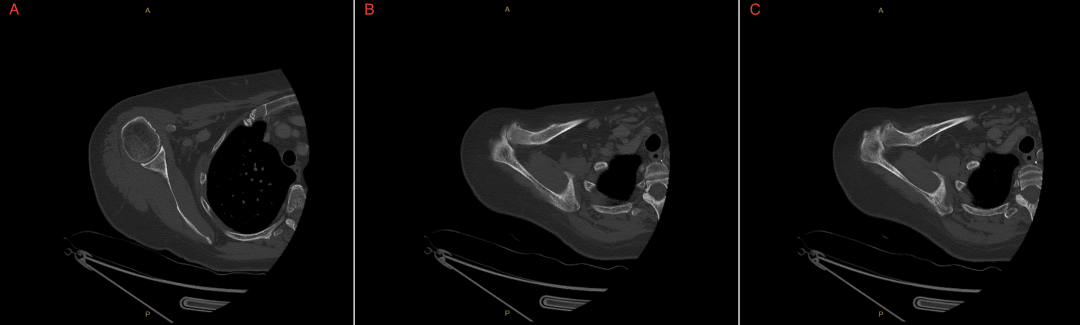

影像学检查:右侧肱骨、前臂增强CT(图1-图3)及左手X线摄片(图4)未见急性结构性或血管性病变;左手广泛存在退行性改变。

图1 肱骨轴位CT骨窗与Ⅳ对比骨窗右侧肱骨轴位CT图像(Ⅳ造影)